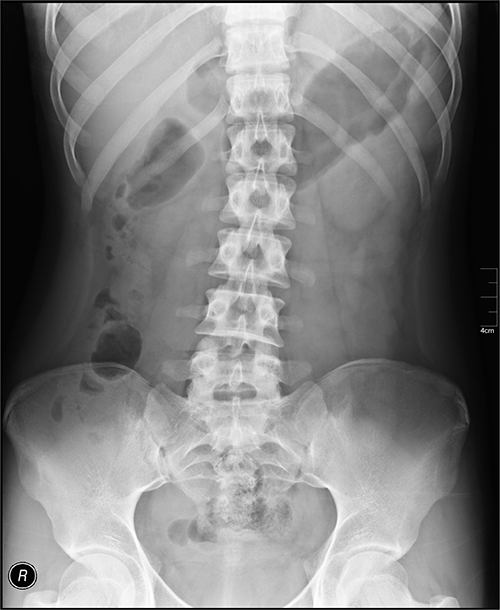

An abdominal X-ray is a non-invasive imaging technique that uses low-dose radiation to create images of the structures inside your abdomen. It primarily shows gas-filled organs (like intestines), calcified structures (like kidney stones), and bones (like spine and pelvis). While excellent for detecting bowel obstructions, free air, and calcifications, abdominal X-rays have limited ability to differentiate between soft tissues, which often appear as subtle gray shadows.

Radiologists evaluate abdominal X-rays by systematically examining four key areas: gas patterns, calcifications, bone structures, and soft tissue outlines. The interpretation requires understanding both normal appearances and recognizing deviations that might indicate pathology: